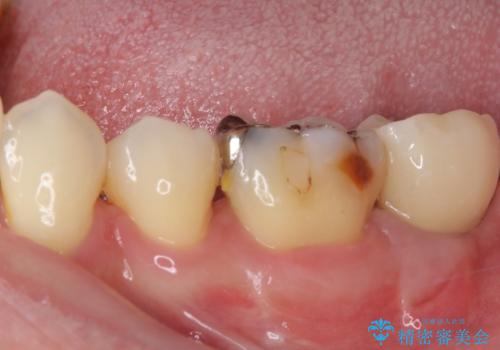

- 左下の奥歯に違和感を感じて来院された患者様です。

診察をした結果、歯根にまで及んだ虫歯と歯周病による著しい骨欠損が認められ、抜歯をせざるを得ない状況でした。